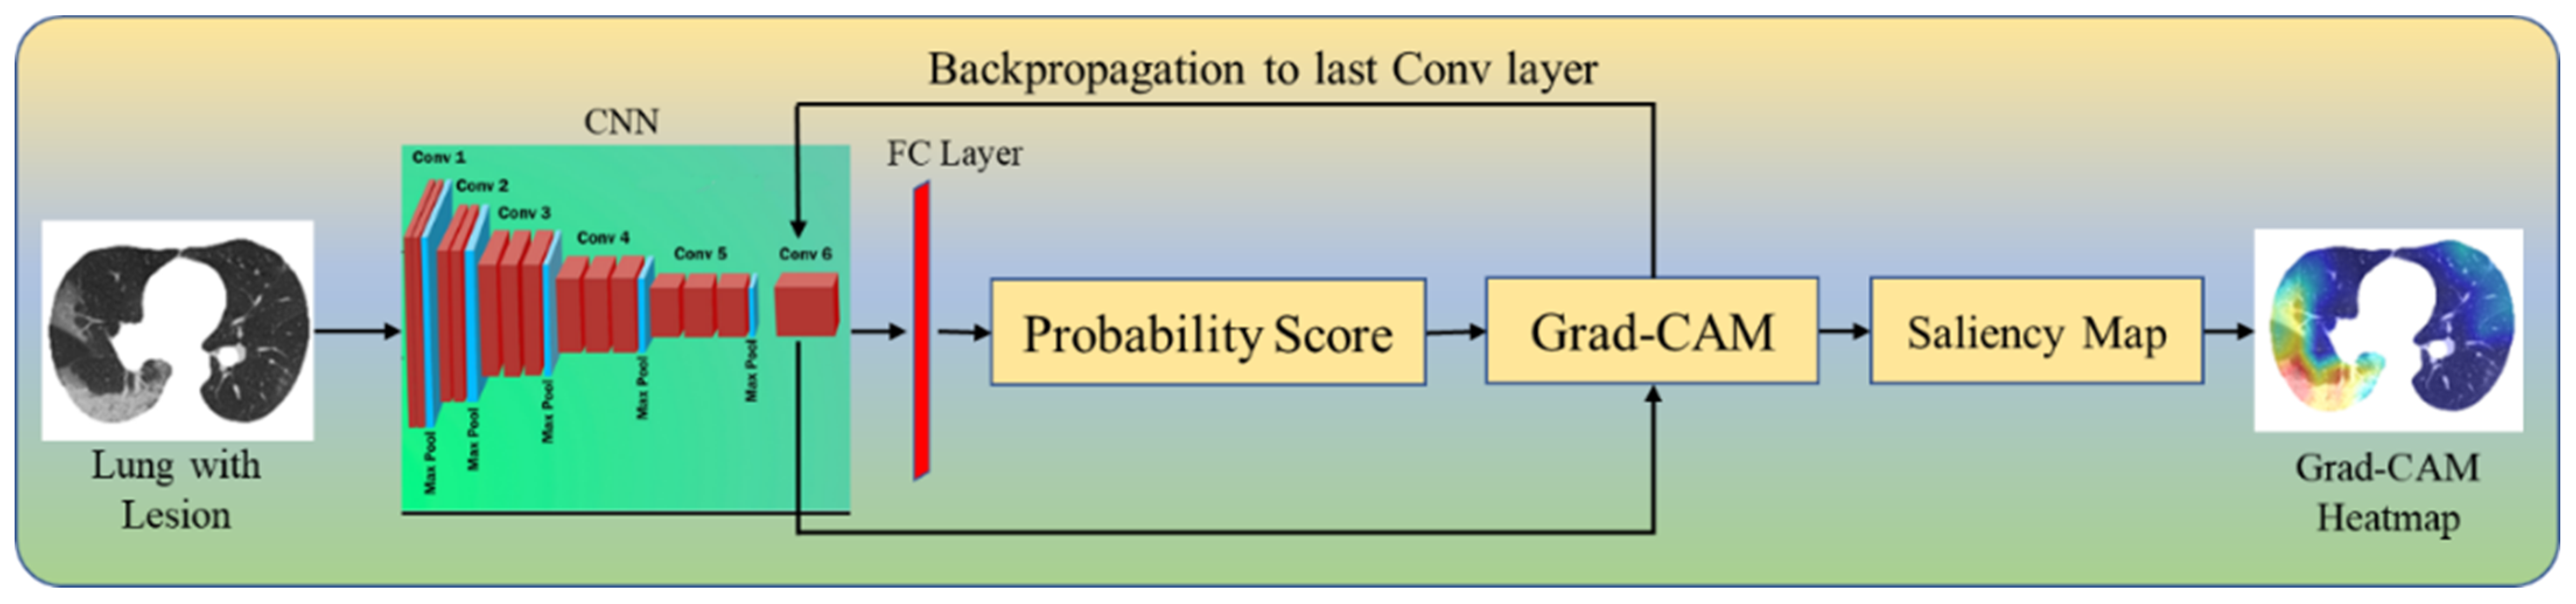

2.4. Explainable Artificial Intelligence System for COVID-19 Lesion

Four CAM Techniques in Cloud-Based Explainable Artificial Intelligence System